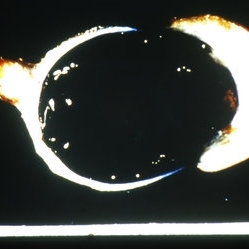

Slide 7-88

Feb 25 2019 by Lancaster Course in Ophthalmology

Totally disorganized ruptured globe.

Condition/keywords: ruptured globe